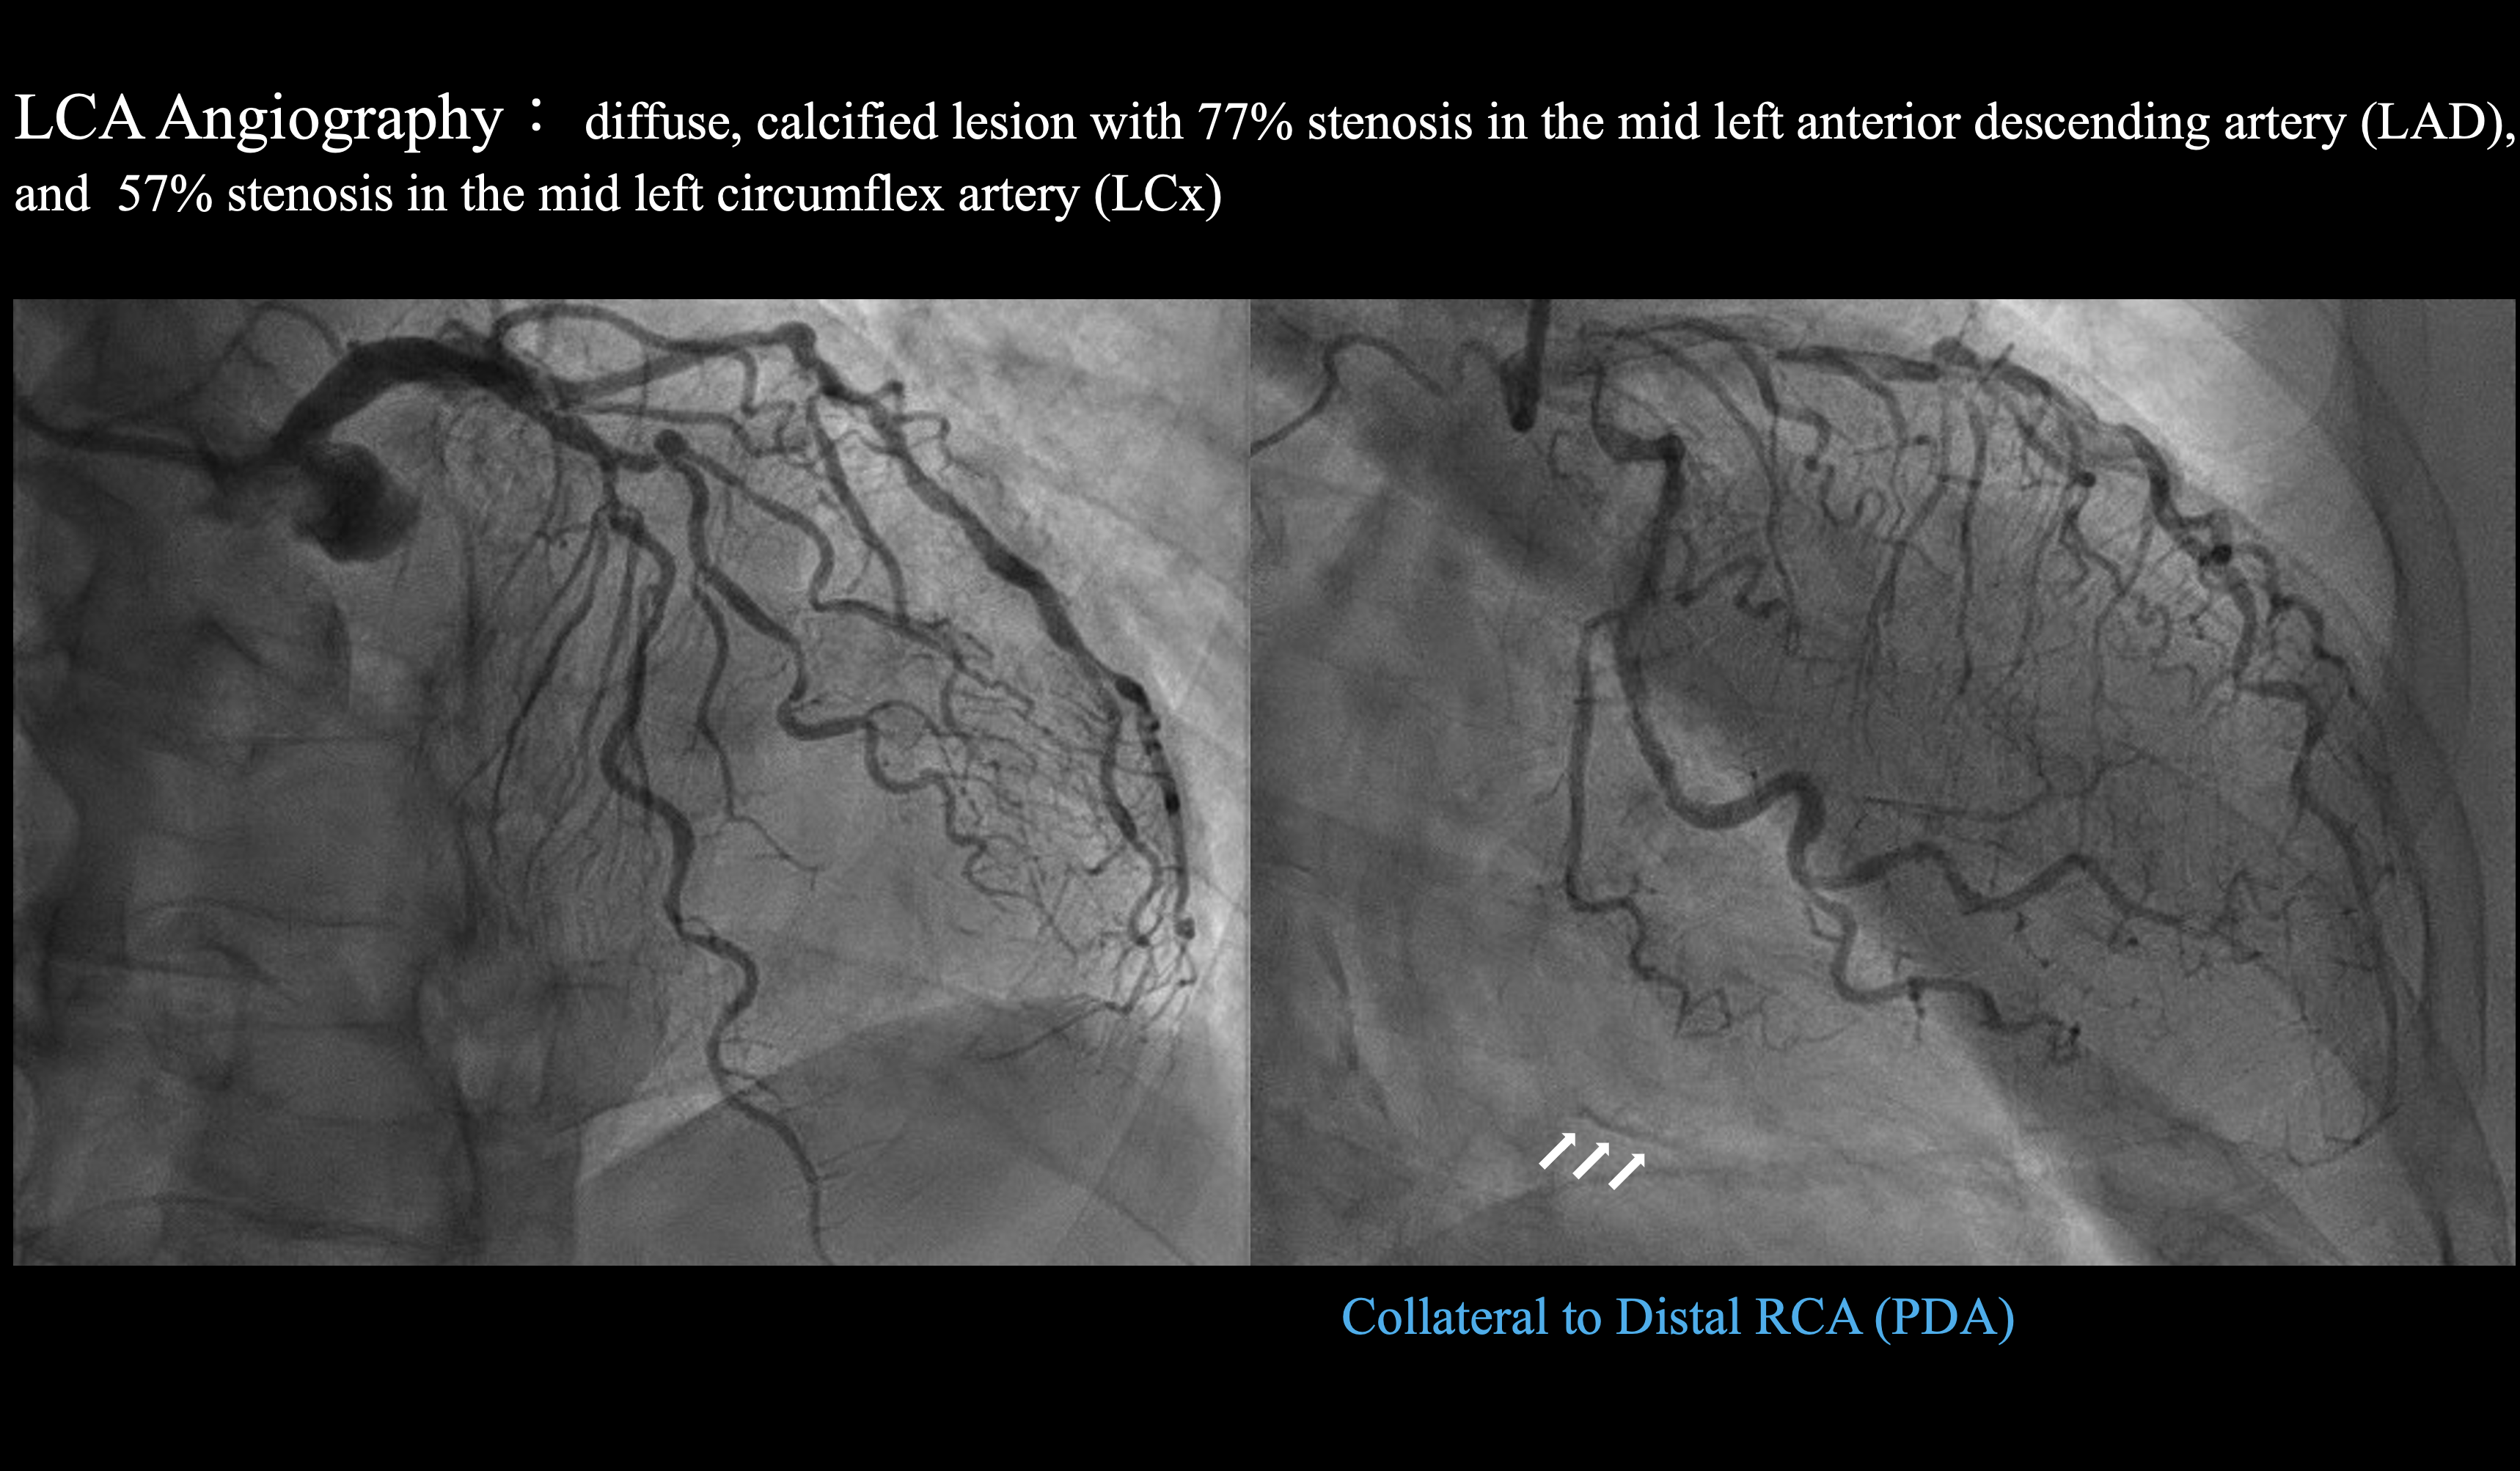

Coronaryangiography revealed a diffuse, calcified lesion with 77% stenosis in the midleft anterior descending artery (LAD), and 57% stenosis in the mid leftcircumflex artery (LCx). Theposterolateral ventricular (PLV) branch showed critical stenosis with TIMI-1flow. Collateral circulation from the left coronary artery (LCA) to the distalright coronary artery (RCA) segment or posterior descending artery (PDA)was faintlyvisible